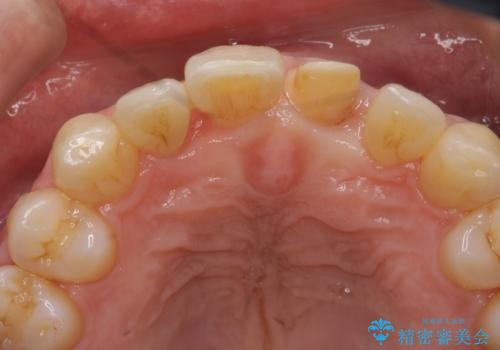

- 前歯の重なったところが虫歯になり、物理的にアプローチが難しい状態でした。

矯正治療前に虫歯を取り、歯並びが良くなってから本格的にセラミック治療を行いました。